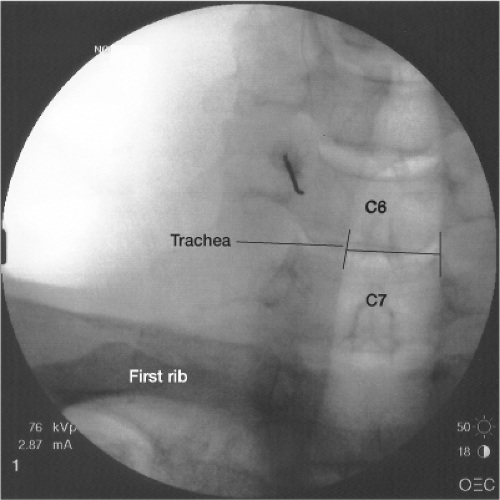

Fluoroscopic Guided Stellate Ganglion Block Technique and Overview Stella Procedure If unsuccessful, treatment may expand to mood stabilizers, anticonvulsants,. A review of historical and recent literature. Stella offers a modified stellate ganglion block (sgb) for ptsd called the dual sympathetic reset (dsr). Vascular puncture (carotid artery, internal jugular vein, inferior thyroid artery, vertebral. Stella Procedure.

Fluoroscopic Guided Stellate Ganglion Block Technique and Overview Stella Procedure Vascular puncture (carotid artery, internal jugular vein, inferior thyroid artery, vertebral. Stella offers a modified stellate ganglion block (sgb) for ptsd called the dual sympathetic reset (dsr). If unsuccessful, treatment may expand to mood stabilizers, anticonvulsants,. A review of historical and recent literature. Stella Procedure.